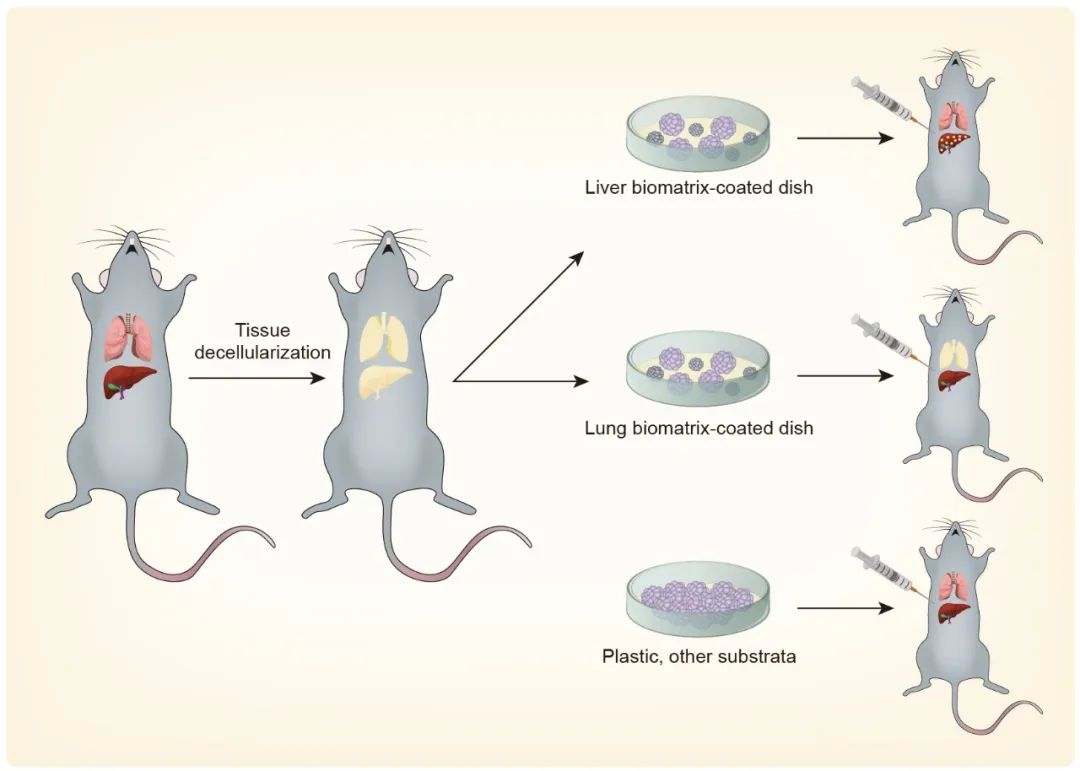

论文插图设计

滑动查看更多 点击查看大图